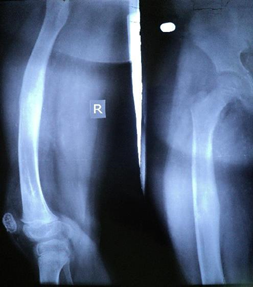

Figure 1 Closed fracture right femoral shaft.

Figure 2 Immediate post-operative x ray of in a 10 year boy.